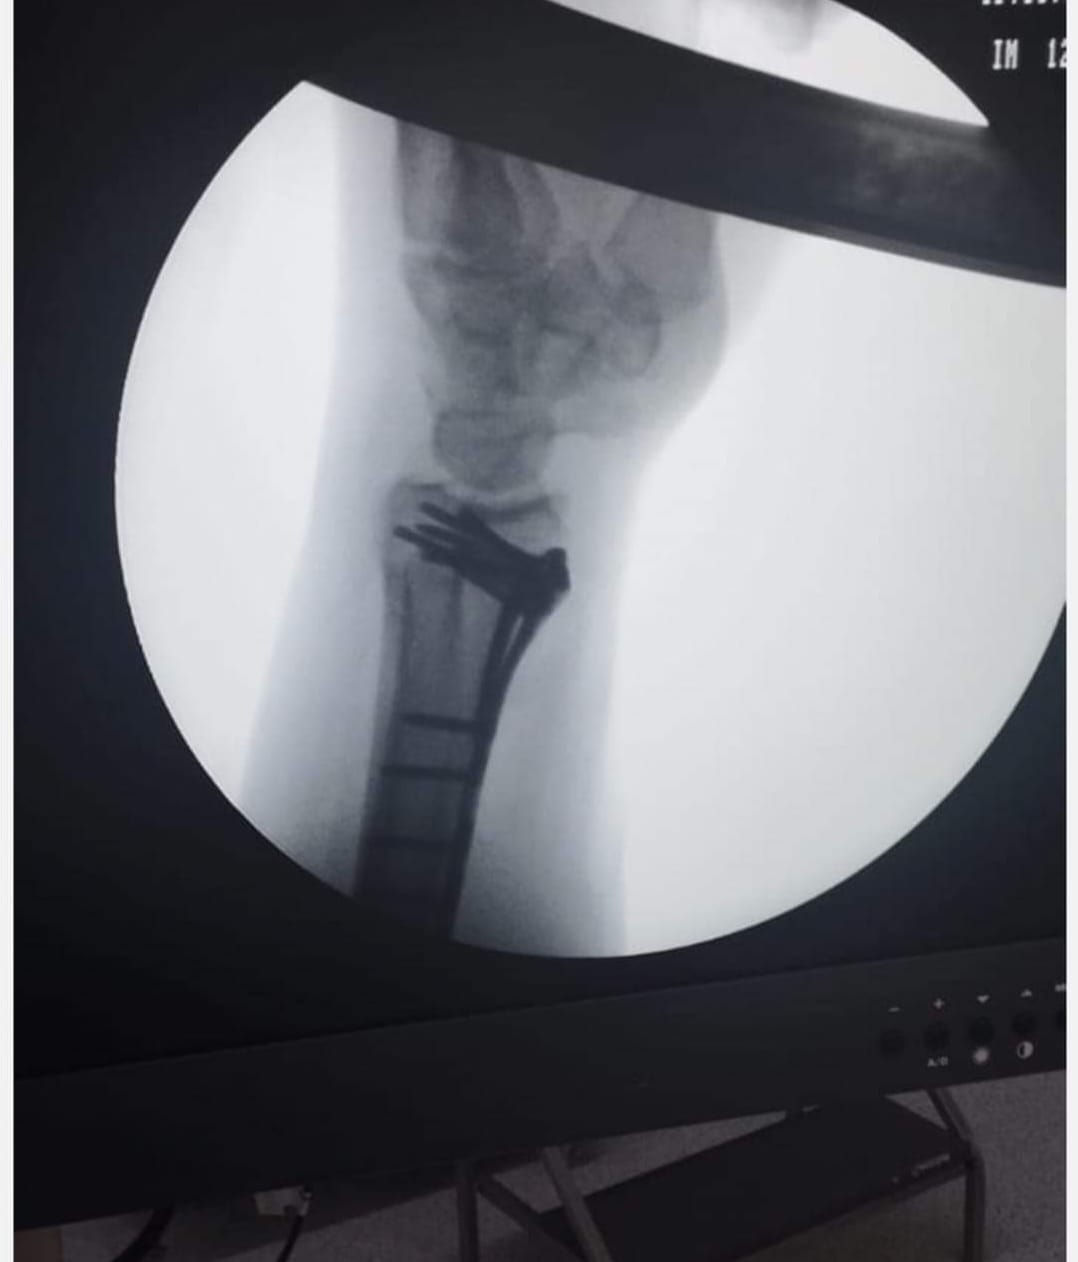

وطنا اليوم -  يقوم بعمليات تثبيت الكسور المعقدة بشكل طاريء وتبديل المفاصل بشكل مبرمج  مما خفف على المواطنين البحث عن أسرة في مستشفيات مركزية رغم صعوبة عمليات العظام من الناحية التقنية في المستشفيات النائية  إضافة الى  استقبال اعداد كبيرة بالعيادات ومعالجة جميع المرضى بالطرق المثلى انه الدكتور الانسان البارع والمتميز يزيد البريزات طبيب العظام في مستشفى الاميرة سلمى / ذيبان عيادة العظام  علماً بأنه كان  مستشفى تحويلي منذ تاسيسه والدكتور البربزات وقبل اربع سنوات في عام 2020  منذ انتقاله للمستشفى يقوم بهذه العمليات ومن بينها  عمليات نوعية لمرضى يعانون من كسور معقدة في الترقوة واجراء عمليات دقيقة ومعقدة لكسور لمرضى في مختلف أنحاء الجسم وعمليات تثبيت الكسور المعقدة وتركيب المفاصل وغيرها الكثير  والديسك " وآلامه وتبعاته وعلاجه وإجراء عمليات معقده وصعبه.

وأجرى الدكتور البريزات عمليات كبرى في جراحة العظام والتي تحتاج إلى مراكز متقدمة ومتطورة. وكذلك العمل على تثبيت أغلب انواع الكسور بطريقة طارئة وتبديل المفاصل بطريقة مبرمجة بما يتناسب مع امكانات المستشفى والتي هي  جزء من  العمليات الدورية بمستشفى الاميرة سلمى في ذيبان  والتي تخفف العبئ على المستشفيات المركزية وعلى المواطن في آن واحد.

وعبر كثير من  المرضى وذويهم عن عظيم شكر هم وامتنانهم للدكتور البريزات على ما بذله ويبذله  من جهود كبيرة واستثنائية في تعامله مع المرضى والمراجعين  ومتابعته الحثيثة لهم والاطمئنان عليهم والتي تكللت جميعها بالنجاح وله الدور الكبير   برفع كفاءة قسم العظام  بالمستشفى بشكل عام والذي  أصبح  متطوراً بالقيام بالعمليات مثل تثبيت الكسور المعقدة و تركيب المفاصل و غيرها.